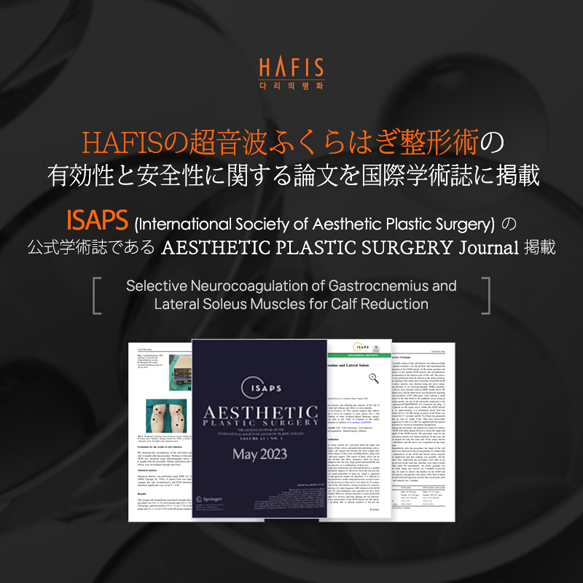

HAFIS CLINIC

ハピス超音波ふくらはぎ形成術の特徴

一度の精密施術で、構造を可視化しながら矯正します。

ハピスの超音波ふくらはぎ形成術は、高解像度医療用超音波機器を用いて、施術前・中・後の全過程をリアルタイムで確認します

これは単なる参考用撮影ではなく、

神経の位置

神経の深さ

筋肉の厚さ

血管分布

筋膜構造

をリアルタイム映像で確認しながら行う精密施術です。

従来法が解剖学的平均位置や電気刺激反応に依存していたのに対し、

ハピスは個々の実際の構造を直接確認しながら行う画像誘導施術(Ultrasound-guided procedure)です。

この違いは、結果と安全性において決定的な差を生み出します。